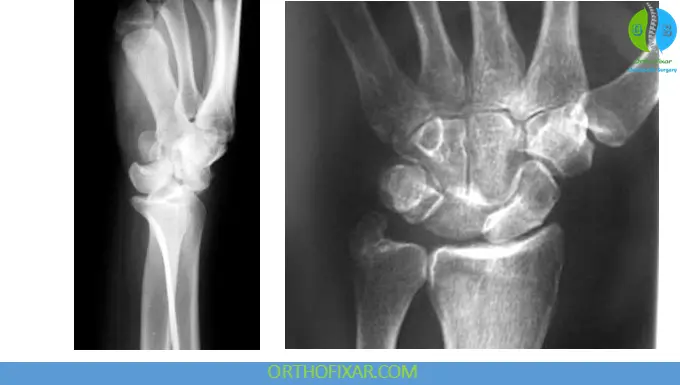

Radiographic Evaluation

Standard Imaging

- PA view

- Lateral view (most important)

- Oblique view

Key Radiologic Signs

PA View:

- Disrupted Gilula lines

- Scapholunate gap > 3 mm (“Terry Thomas sign”)

- Triangular (“piece-of-pie”) lunate appearance

Lateral View:

- Misalignment of capitate and lunate

- “Spilled teacup sign” → indicates volar lunate dislocation

CT Scan:

- Useful for detecting associated fractures and defining injury pattern